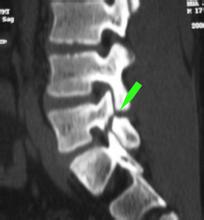

临床上腰椎滑脱是比较常见的腰椎病,可以分为不同的类型,不同患者的腰椎滑脱表现症状也有所不同。下肢灼痛是腰椎滑脱患者常有的表现,可让患者感觉到下肢不仅疼痛,而且就像是灼烧一样的痛。》》》百看不如一问,咨询专家如何对症治疗

2、当滑脱程度大的时候,可压迫邻近神经根,可引发下肢的放射痛或麻木感,而且痛麻症状可出现在两侧,但症状表现轻重不等。当腰椎滑脱患者的马尾神经受牵拉时,患者的下肢及鞍区可以出现感觉麻木,肌肉无力或肌萎缩症状。》》》清晰了解自身病情,点击在线咨询专家

3、滑椎棘突和上位椎体棘突间,可触及有台阶感,局部压痛。如神经受累的时候,可以表现为肌力减弱,膝、跟腱反射减弱或消失症状。》》》如何确诊自身病情,点击咨询